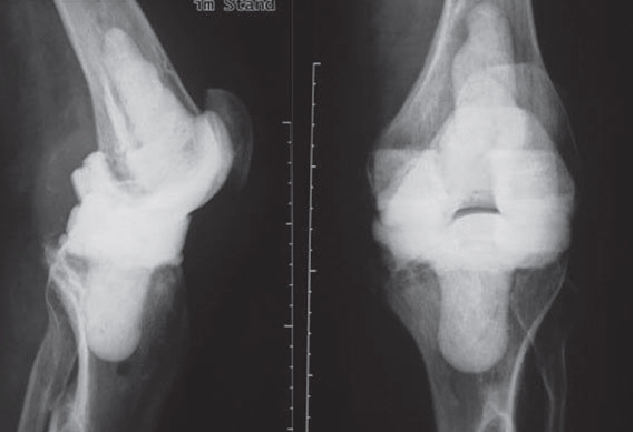

However, infections often go unnoticed for many weeks, so that removal of the prosthesis is unavoidable. Depending on the pathogen and its sensitivity, a placeholder containing antibiotics is then implanted, which remains in place for 6 weeks. Antibiotics in tablet form must then also be taken for this period. However, it is not necessary for a patient to remain in the hospital during this entire period. If home care is not possible, for example, it is also possible to organize this in close cooperation with our social services. After 6 weeks it is generally possible to reimplant a prosthesis, provided that the blood values show that the infection is under control. Antibiotics must then be taken again for 6 weeks after surgery. Which antibiotics are taken is determined in close cooperation with colleagues in microbiology and clinical pharmacology, with whom regular rounds and therapy checks are carried out. These therapeutic measures are carried out in a special area of the clinic using the most modern methods.